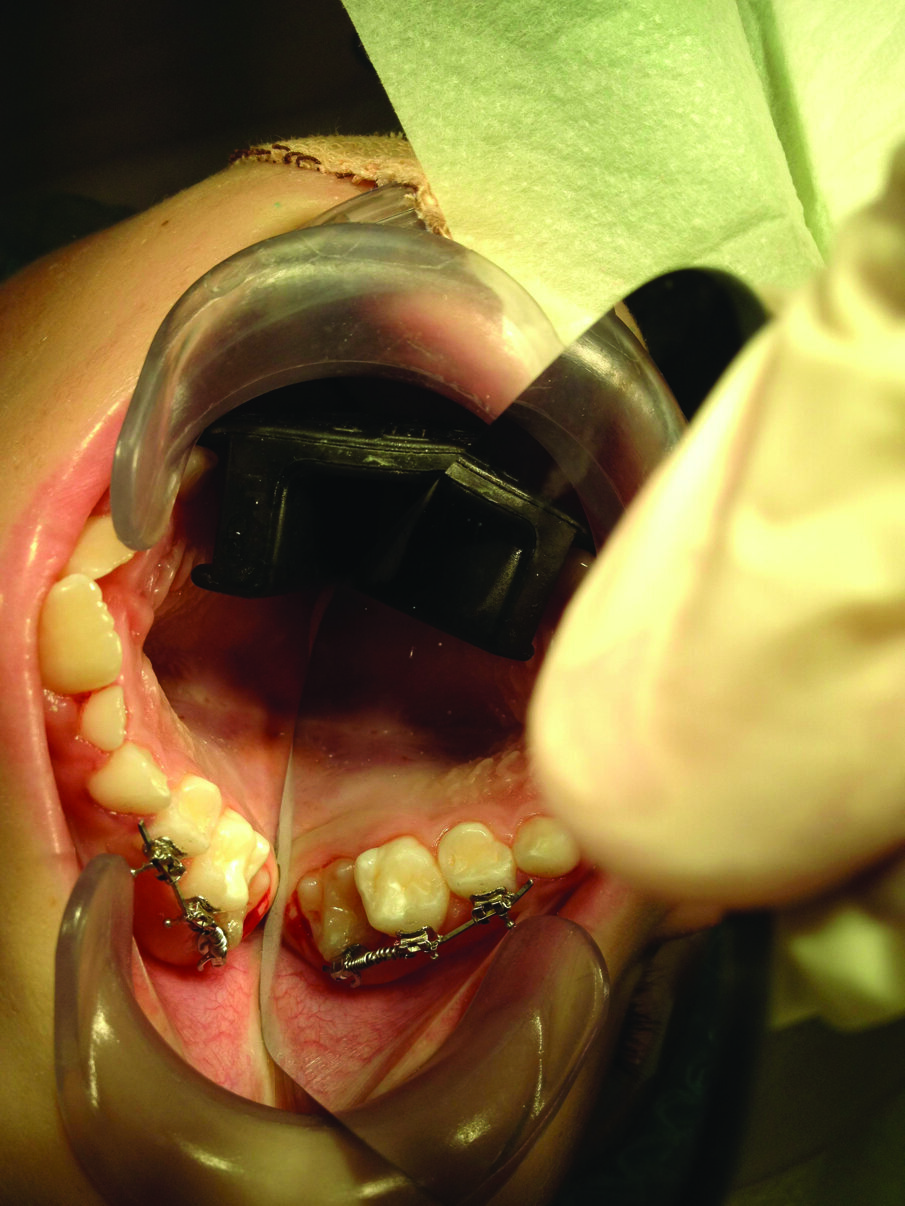

Figure 3: A plastic orthodontic separator is placed to attempt to correct a mild ectopic eruption in the upper right first permanent molar.

Figure 4: An ectopically erupted first primary molar corrected by an open coil spring fixed orthodontic appliance.

Treatment depends on how severe the impaction appears clinically and radiographically. For mildly impacted first permanent molars, where little of the tooth is impacted under the primary second molar, elastic or metal orthodontic separators can be placed to wedge the permanent first molar distally4, Figure 3. For more severe impactions, distal tipping of the permanent molar is required. Tipping action can be accomplished with brass wires, removable appliances using springs, fixed appliances such as sectional wires with open coil springs, Figure 4, sling shot-type appliance3, Figure 5, a Halterman appliance5, Figure 6, or surgical uprighting6.